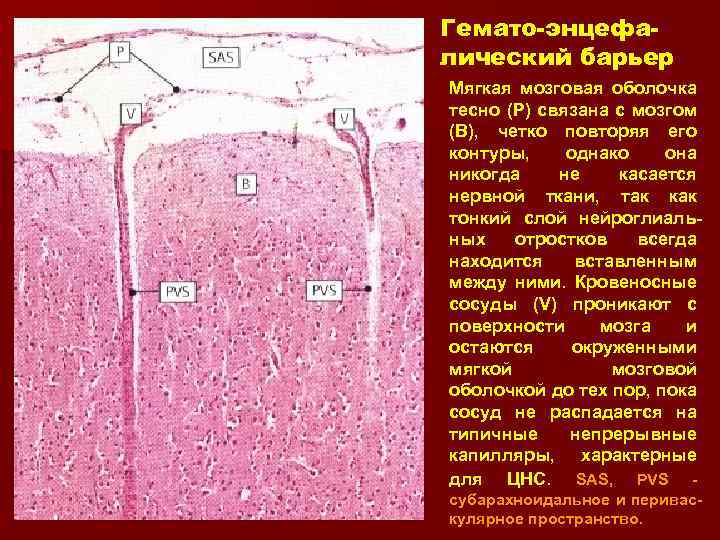

Гемато-энцефалический барьер Мягкая мозговая оболочка тесно (Р) связана с мозгом (В), четко повторяя его контуры, однако она никогда не касается нервной ткани, так как тонкий слой нейроглиальных отростков всегда находится вставленным между ними. Кровеносные сосуды (V) проникают с поверхности мозга и остаются окруженными мягкой мозговой оболочкой до тех пор, пока сосуд не распадается на типичные непрерывные капилляры, характерные для ЦНС. SAS, PVS субарахноидальное и периваскулярное пространство.

Гемато-энцефалический барьер Мягкая мозговая оболочка тесно (Р) связана с мозгом (В), четко повторяя его контуры, однако она никогда не касается нервной ткани, так как тонкий слой нейроглиальных отростков всегда находится вставленным между ними. Кровеносные сосуды (V) проникают с поверхности мозга и остаются окруженными мягкой мозговой оболочкой до тех пор, пока сосуд не распадается на типичные непрерывные капилляры, характерные для ЦНС. SAS, PVS субарахноидальное и периваскулярное пространство.